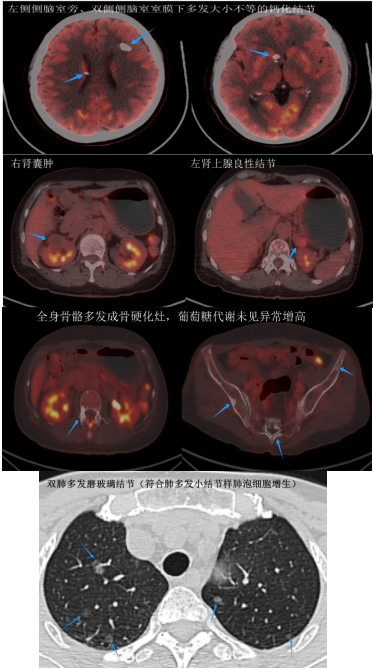

经过仔细的分析,医生们得出了结论:彭女士头部左侧侧脑室旁、双侧侧脑室室膜下多发大小不等的钙化结节,双肺多发磨玻璃结节及实性结节影,符合肺多发小结节样肺泡细胞增生的特征;同时,她的颅骨、胸骨、脊椎、骨盆骨等等多处存在骨质增生硬化的改变,双肾多发囊肿,左侧肾上腺存在结节。然而,这些病变在PET/CT图像上均未显示出葡萄糖代谢的异常增高,这意味着这些病变很可能并非恶性病变的多发转移。

而彭女士身上这些病灶都是一种叫结节性硬化症的罕见遗传性疾病导致的。结节性硬化症源于患者体内TSC1/TSC2基因突变,能够影响到人体几乎所有的器官和系统,其中皮肤、脑、肾脏、肺和骨骼是最常见的受累部位。由于正常实质被多种类型细胞结构所替代,患者体内各器官会形成错构瘤或结节,进而引发相应器官或系统的功能障碍。在个别情况下,部分病灶甚至会诱发恶变。

幸运的是,PET/CT检查为这种多系统疾病的检测和评估提供了强大的支持。一方面,由于PET/CT检查的范围广泛,能够显示出结节性硬化症所累及的大部分器官病变;另一方面,它还能根据葡萄糖代谢程度对这些病变进行准确的良恶性判断。